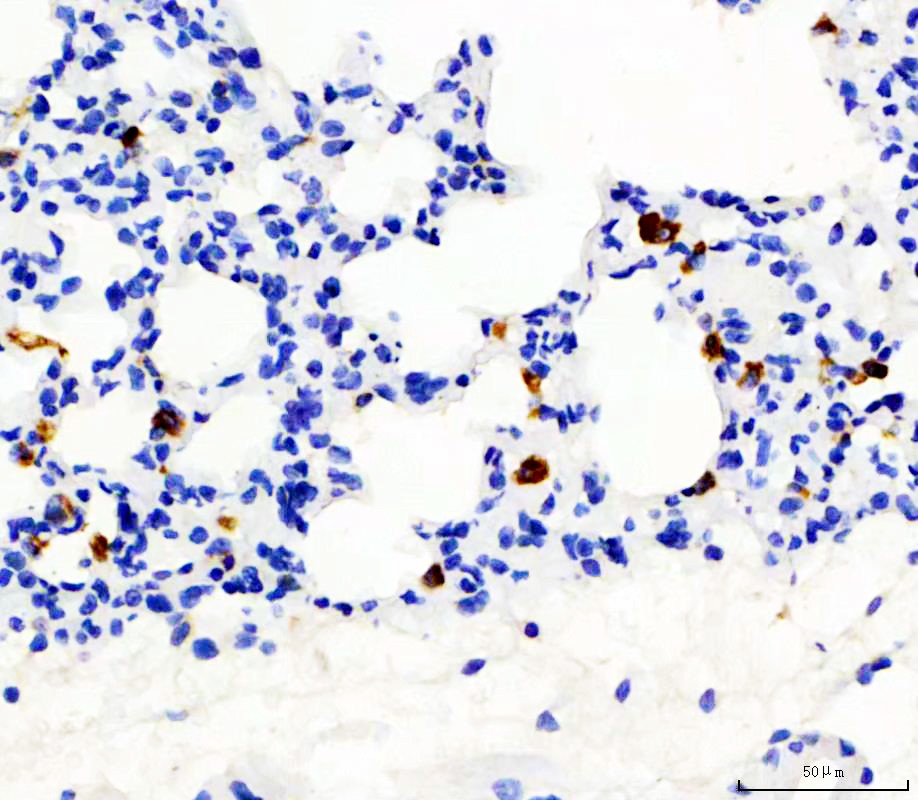

IHC analysis of CD68 using anti-CD68 antibody (BA3638) .

CD68 was detected in a paraffin-embedded section of rat lung tissue. The tissue section was incubated with rabbit anti-CD68 Antibody (BA3638) at a dilution of 1:200 and developed using HRP Conjugated Rabbit IgG Super Vision Assay Kit (Catalog # SV0002) with DAB (Catalog # AR1027) as the chromogen.